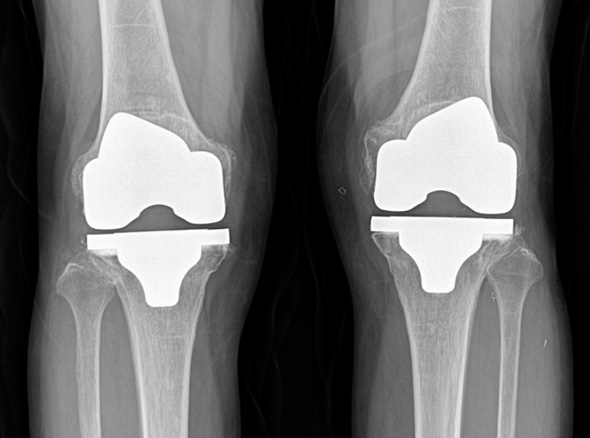

손상된 무릎 뼈를 제거하고, 그 부위에 특수 소재의 금속 재질로 구성된 인공관절을 삽입하는 수술을 시행할 수 있습니다.

관절연골이 망가져 쓸 수 없을 때 관절기능 회복을 위해 시행하며, 인공관절의 수명은 20~30년 정도 됩니다.

세계적인 의료기기 기업 스트라이커(Stryker)사의 특화된 임플란트를 사용합니다.

정밀한 설계, 내구성, 생체 적합성 등의 장점을 두루 갖추어 전 세계적으로 가장 많이 사용되고 있습니다.